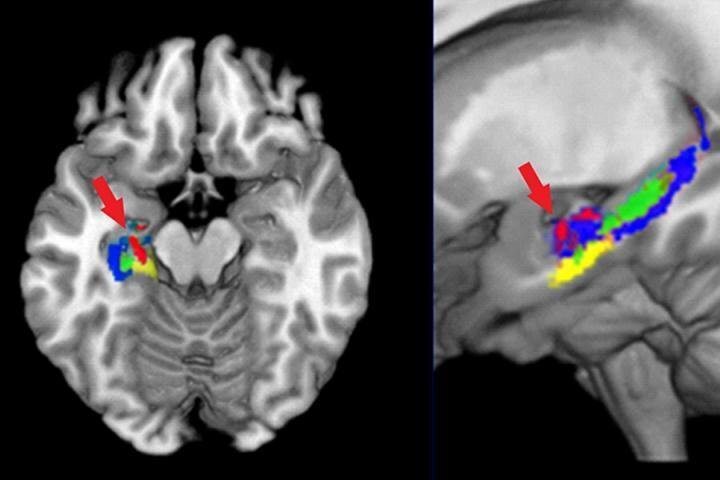

Перед вами — схема активности в мозге не-химика, который занимается выучиванием новых формул органических молекул. Три способа визуализации позволили установить новые детали в процессах обучения в головном мозге.  Подробности читайте на нашем портале в ближайшее время. Credit: Marcel Just and Timothy Keller Converging measures of neural change at the microstructural, informational, and cortical network levels in the hippocampus during the learning of the structure of organic compounds

Just, M.A. & Keller, T.A. Brain Structure & Function (2019). 10.1007/s00429-019-01838-4